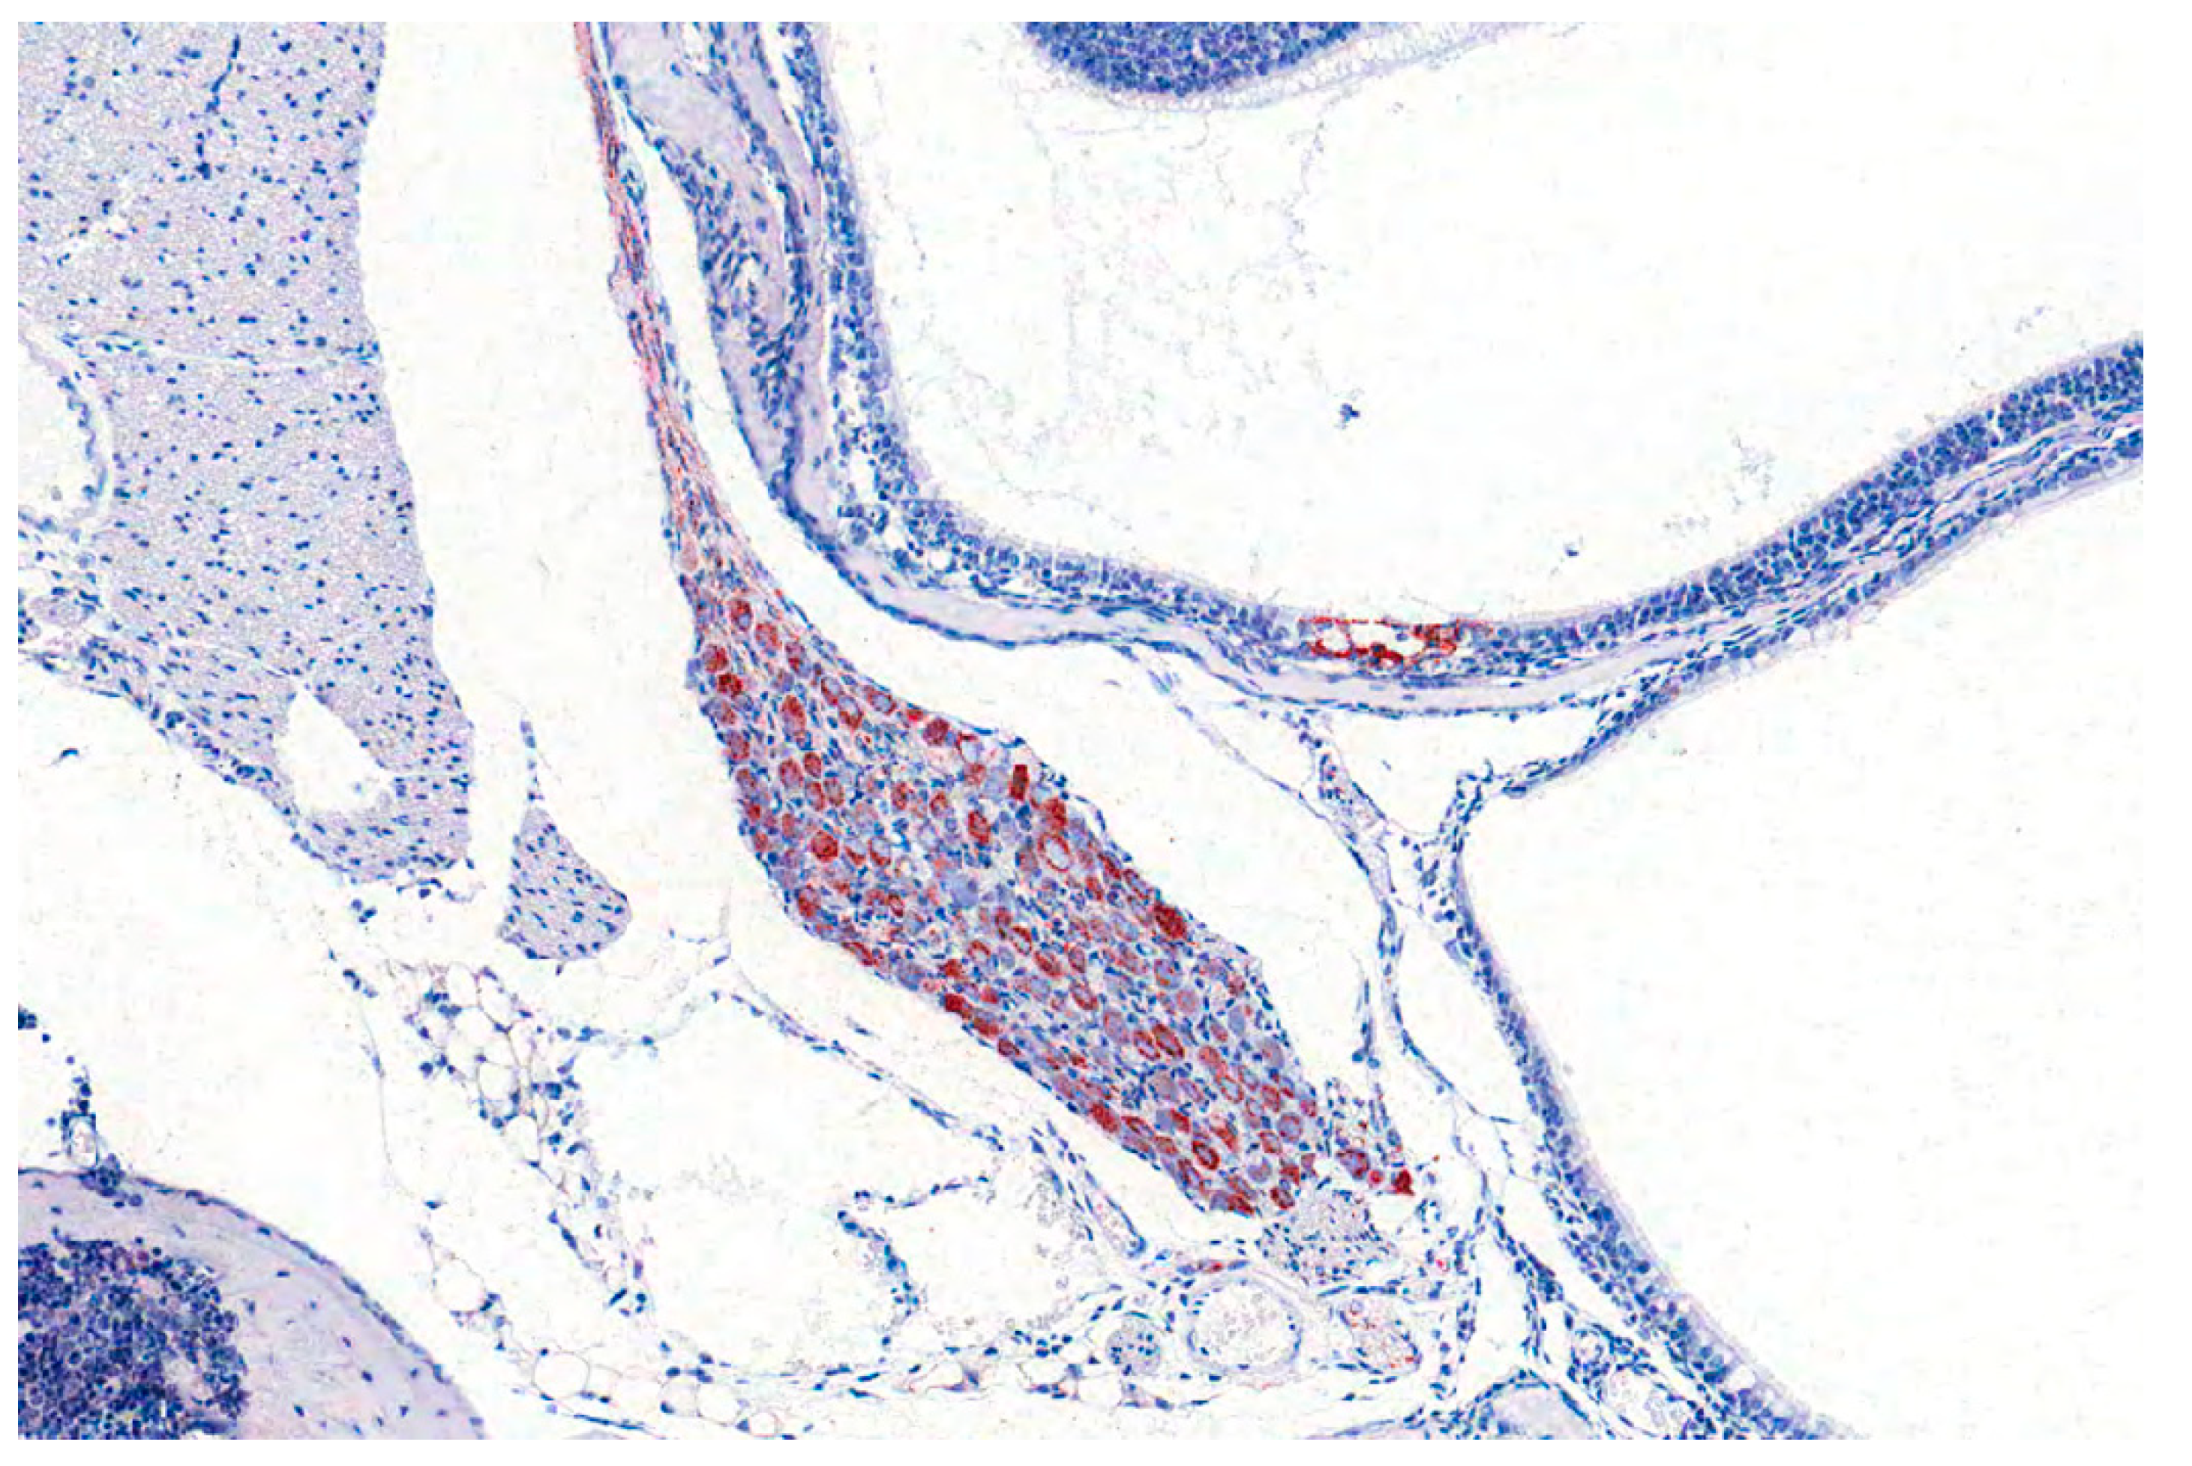

Figure 11.

Pterygopalatine ganglion of a mouse infected experimentally with PRV. PRV-antigen reveals numerous positive neurons (red labelling by immunohistochemistry).

Rats and mice are less susceptible than rabbits. Compared to mice, rats display a greater resistance to PRV infection, since successful oral inoculation requires 106 PFU and mucosal injuries. In mice, 104 PFU is the minimal infectious dose, dependent on the virus strain [111]. Mice can be infected by various inoculation routes including: i.n., p.o., i.o., i.c., i.v., i.m., intraperitoneal (i.p.), s.c. or via foot pad [24,25,27,115,116,117,118,119,120,121]. Depending on the inoculation route, the incubation period of AD in mice is longest after intranasal or intraocular infection [115]. After intracerebral infection, mice are recumbent and comatose and die within two days post infection (p.i.). A generalized pruritus can be observed after intravenous and intraperitoneal inoculation with phases of frequent „face-washing“ [115]. With disease progression pruritus and edema at the head worsen, which is followed by collapse of the animals. Mice infected intranasally do not show skin lesions, but appear to be blind. They also show violent, spasmodic movements before they die. This is in contrast to previous experiments in mice, where intranasal infection leads to a more severe clinical picture [24,25,27,121]. Mice show hunching, anorexia, depression, hyperactivity and severe pruritus at the head (Figure 10). Some develop excitations, convulsions and dyspnea. The animals have hemorrhagic dermal erosions and ulcerations, nasal bridge edema and acute catarrhal conjunctivitis and do not survive longer than 3 d p.i. The same is true for subcutaneous (flank) inoculation in mice [118]. After intramuscular injection, mice exhibit intense pruritus at the inoculation site, collapse and die. Excessive itching, head edema and self-mutilation are also present in mice after intraocular infection [115]. Virus is only detectable in the brain after i.c. or i.o. infection. The spleen shows viral antigen positive cells after i.v. infection, whereas PRV can be found in the kidney after i.m., i.v. and i.p. and to some extent after i.n. infection [115]. In contrast, Klopfleisch et al. [25] did not identify viral antigen in other tissues than the brain and epithelial cells in the nasal mucosa after i.n. infection. Immunohistochemically, PRV antigen is localized in the respiratory and nasal gland epithelium, trigeminal ganglion, brainstem and to some extent in the midbrain. Further, the sympathetic superior cervical ganglion as well as the parasympathetic pterygopalatine ganglion are affected [24,25] (Figure 11). In addition, the olfactory epithelium, the vomeronasal organ as well as blood vessel walls are positive for viral antigen [121] as well as salivary glands [27]. Inflammation is only mild and occasionally present in the nose and superior cervical ganglion [27]. Subcutaneous inoculation results in infection of the brainstem and the cerebellum [118], whereas after foot pad inoculation virus can moreover be isolated from the sciatic nerve, lower spinal cord, adrenal gland, coeliac ganglia and paravertebral ganglia [119]. This is in line with inflammatory changes in dorsal root ganglia and at the site of inoculation [120].